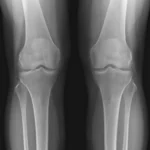

Osteoarthritis

X-ray shows joint space narrowing, bone spurs (osteophytes), and changes in bone density that indicate degenerative joint disease, commonly affecting knees, hips, and hands.

Different X-ray views provide different diagnostic information. For example, a chest X-ray is typically taken from two angles, posteroanterior (PA) and lateral, to give a comprehensive view of the lungs, heart, and mediastinum. Bone X-rays may require multiple views to fully assess a fracture or joint abnormality. Your radiologist will determine the appropriate views based on your clinical indication.